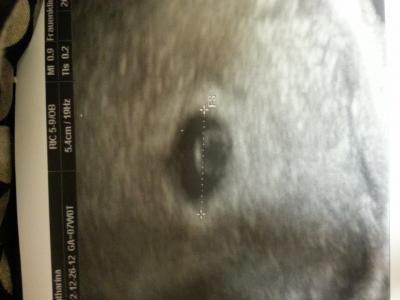

Hay, Also bin ins kh gefahren... Die haben direkt us gemacht und man hat eine fruchthohle mit dottersack gesehen. Die größe der fruchthohle entspricht 5+0 :)) Einen Embryo konnte man leider noch nicht sehen, aber macht nix jetzt weiß ich das alles ok ist. Bin total erleichtert :)) Schönen Abend euch noch *-*

Bild zu Bericht vom kh - Forum für August - Mamis